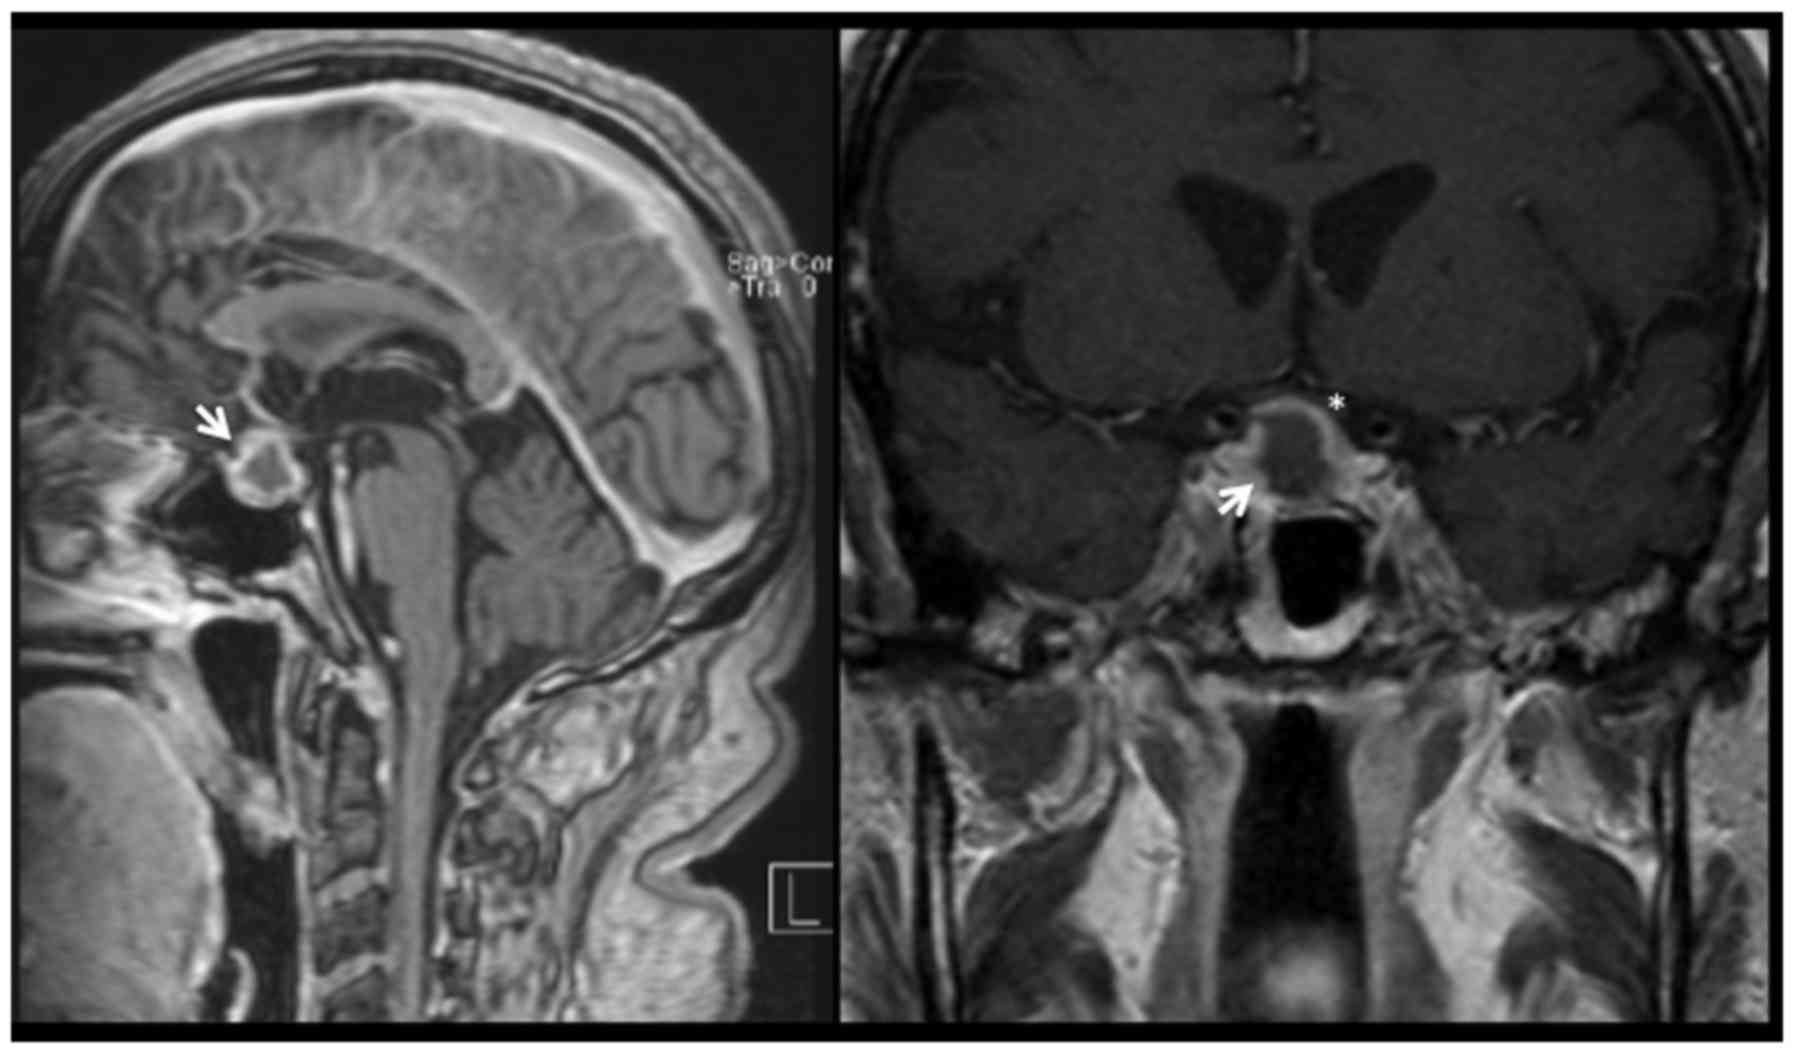

A 77-year-old man presented to the University Hospital of Lausanne in October 2015 with fatigue and clinical signs of hypogonadism. The clinical presentation was suggestive of hypopituitarism and endocrine tests showed an anterior pituitary dysfunction. Investigation with cerebral magnetic resonance imaging (MRI) demonstrated a sellar lesion with suprasellar extension and no compression of optic structures. He was admitted at the neurosurgical department and initial management consisted of hormonal replacement therapy and a ‘watch-and-wait’ approach. One year after his initial presentation (October 2016), the patient returned to the emergency department with a thunderclap headache. A cerebral MRI demonstrated pituitary apoplexy (Fig. 1). There were no visual deficits on clinical examination and we decided to continue the regular monitoring and follow-up. Over 6 weeks of follow-up the patient started complaining of visual symptoms, secondary to a progressive growth of the pituitary lesion with compression of the optic chiasm (Fig. 2). Ophthalmological examination confirmed a right temporal quadrantanopia.

Figure 1.

Sagittal (left panel) and coronal (right panel) views of a gadolinium enhanced T1-weighted cerebral magnetic resonance imaging. This shows a sellar lesion with peripheral contrast enhancement and a central hypointense core which is compatible with pituitary apoplexy (white arrow). The lesion provoked a sellar enlargement and presented an extension in the suprasellar space. The optic chiasm is visible immediately superior to the tumor, with no clear compression at imaging (the left optic nerve is marked with an asterisk).